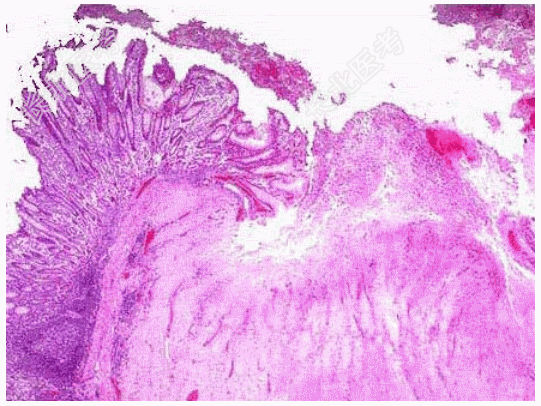

- [材料题] 患者,男,50岁。诉返酸、嗳气,上腹部不适1年。胃镜见胃窦部一直径1cm的溃疡。取活检3小块。镜下如图,病理诊断为慢性胃溃疡。